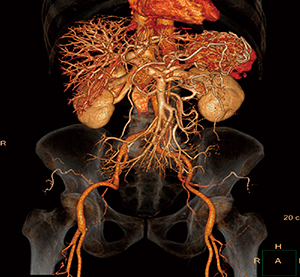

1.CTA画像の高画質化

従来の再構成法では画像ノイズの発生が原因で臨床応用が難しかったCTA撮影において高分解能イメージング3),4)の相性が良く,多くの施設で使用されている(図4)。

図4 IMR Platinumを用いたCTA画像

100kV,232mAs,CTDIvol:8.9mGy

門脈相の画像だが,ノイズ低減により肝動脈も描出されている。